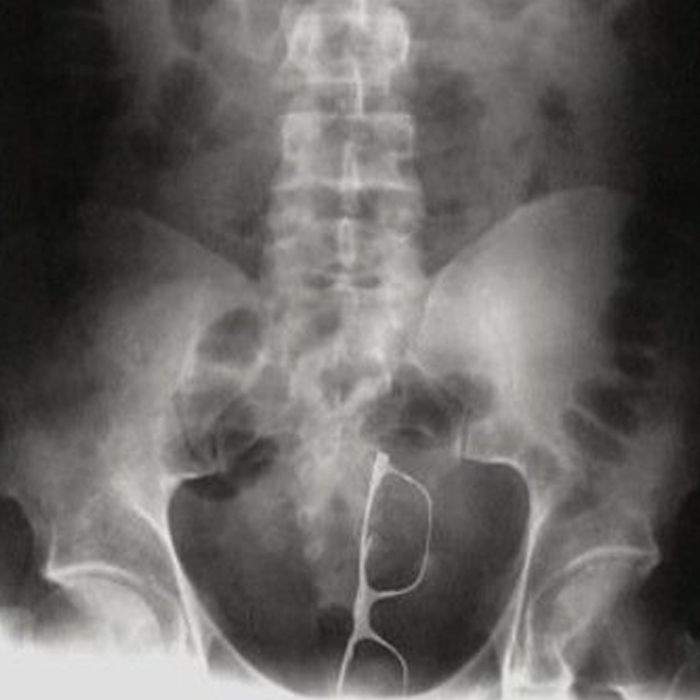

▼墨鏡出現在它最不該出現的地方,一片漆黑的地方戴什麼墨鏡

圖片來自:ems1